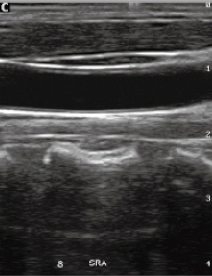

Технология SRA - подавляет шумы, оптимизирует контраст, снижает зернистость изображения, тем самым делает его более точным, что облегчает анализ (слева - без SRA, справа - режим SRA)..